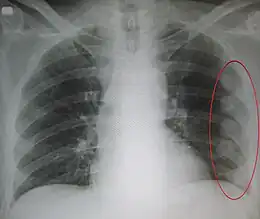

Radiographie de multiples fractures costales gauches (entourées d'un ovale)